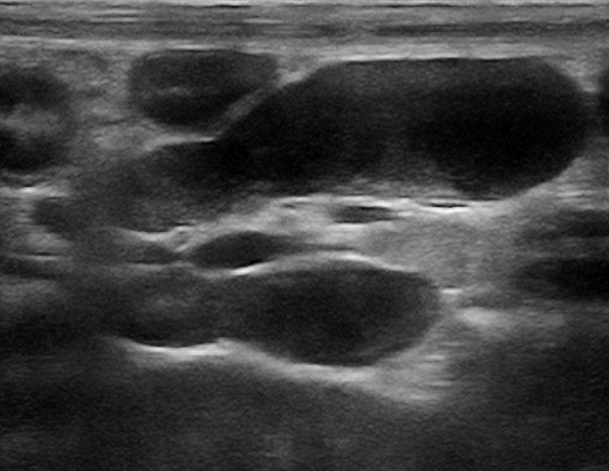

EVOLUÇÃO: INDICAÇÃO DE EXAME ULTRASSONOGRÁFICO

- Foi realizado exame ultrassonográfico abdominal que revelou presença de discreta quantidade de líquido livre em cavidade abdominal, linfonodos esplênico e mesentéricos acentuadamente aumentados e de ecotextura heterogênea. Visibilizou-se uma estrutura parenquimatosa aderida a um segmento de alça intestinal jejunal, homogênea, de formato ovalado, medindo 2,14cm x 1,44cm, vascularizada ao Doppler colorido e que invadia e obstruía parcialmente o lúmen intestinal, sugerindo processo neoplásico.

Linfonodo mesentérico 1º exame

Plissamento de alça 2º exame